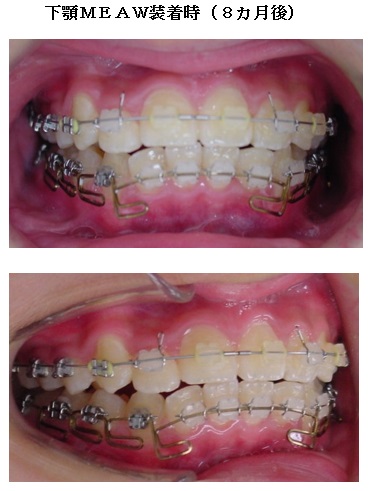

顎偏位の症例はMEAW(マルチループ)の得意としている症例です。

治療は上顎から矯正装置を装着していきます。その後下顎の矯正装置を装着します。

この過程で歯並びが整いMEAW(マルチループ)を装着しやすくなります。

MEAW(マルチループ)を使用する事で顎偏位により左右の咬合高径(咬み合わせの高さ)の改善をしています。その治療により左右の顎のズレが改善されます。

顎偏位は上顎前突や下顎前突のように顎骨の前後のズレではなく左右のズレである為に歯を抜いて治療する事が出来ないストレートワイヤー法では治療が困難な症例です。

当院はMEAW(マルチループ)により効率的に治療を進めています。